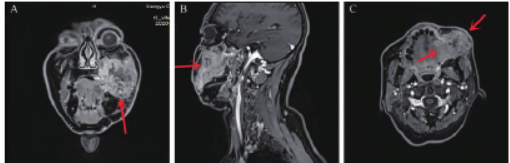

颌面部及颈部磁共振成像

(magnetic resonance imaging,MRI)和CT(图2、3)示:左侧颊癌术后改变,左侧颊部术区新见一大小约5.2 cm×5.1 cm 肿块,考虑颊癌复发。

图2 口腔、颈部MRI 平扫及增强扫描图像。A. 冠状位MRI 示患者术区新发肿块大小约5.4 cm×3.9 cm,病变增强呈不均匀明显强化,中心可见无强化区(红色箭头所指);B. 矢状位MRI 示患者术区新发肿块向上突入上颌窦窦腔内,邻近左侧眶底(红色箭头所指);C. 横断位MRI 示患者术区新发肿块向内与舌体分界不清,向外侵及皮肤(红色箭头所指)。